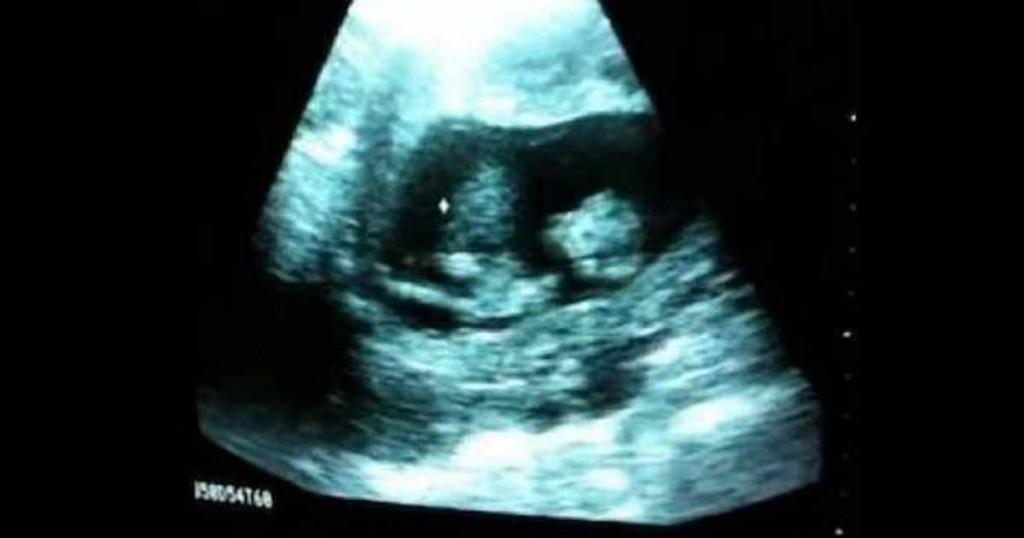

Η εγκυμονούσα μαμά μαζί με τον σύζυγό της επισκέφτηκαν το γυναικολόγο για να δουν μέσα από το καθιερωμένο υπερηχογράφημα για λίγο τη κόρη τους.

Ποτέ δεν θα μπορούσαν όμως να περιμένουν αυτό που παρακολούθησαν: Η αγέννητη κορούλα τους έπαιζε μέσα στη κοιλιά της μαμάς της!

Αν και είναι αρκετά εκπληκτικό να το βλέπει κανείς, στη πραγματικότητα είναι κάτι αρκετά κοινό.Τα μωρά μέσα στη κοιλιά της μητέρας τους, κάνουν πολλά αστεία και ασυνήθιστα πράγματα.Μπορεί να τα δείτε να πιπιλίζουν τους αντίχειρες τους, να φτερνίζονται, να ονειρεύονται και να τρομάζουν από τους έντονους θορύβους και τις απότομες κινήσεις της μαμάς.Φυσικά, μπορούν και να παίξουν, όπως θα δείτε στο βίντεο. Σύμφωνα με τους περισσότερους γιατρούς, αν ένα μωρό παίζει και κλωτσάει, όπως το συγκεκριμένο μωράκι, τότε στη ζωή του θα είναι ευτυχισμένο, υγιή και ακμαίο!